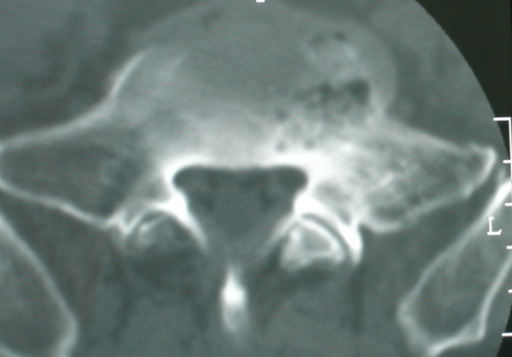

以下是引用jinguoji在2008-6-3 20:20:00的发言:[br]双上肺弥漫性小结节影,纵隔窗内钙化淋巴结影,考虑血播性tb可能性较大,不除外肺ca可能。腰椎考虑退变。

以下是引用卜一在2008-6-3 19:33:00的发言:[br]双肺结节,以双上肺分布为多,期间搀杂片状致密影及索条致密影。考虑:继发性肺结核伴血型播散可能性大。不除外肺泡ca的可能!另:椎体退变!

以下是引用panyishengct在2008-6-3 21:09:00的发言:[br]双上肺弥漫性小结节影,纵隔窗内钙化淋巴结影,考虑矽肺或/和tb可能性较大,不除外肺ca可能。腰椎考虑退变。 [br][br]